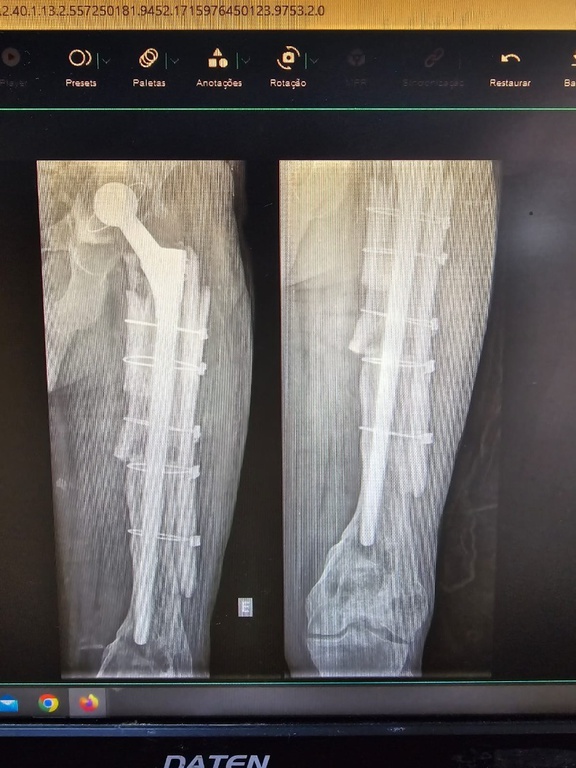

“O procedimento foi um sucesso. Conseguimos reconstruir o fêmur e corrigir o encurtamento do paciente com o uso de uma haste femoral de revisão e réguas ósseas. O paciente andou no mesmo dia da cirurgia, não precisou de UTI e não precisou de transfusão de sangue. Está no sexto mês de pós-operatório, sem dor e sem queixas. Vida normal”, comenta o médico ortopedista do HU-UFMA, Raul Almeida, que é o responsável técnico pelas equipes de transplante de tecido ósteo-condro-fáscio-ligamentoso do HU.

Juarez Sousa foi o 20º de 21 pacientes já beneficiados por esse tipo de transplante no HU-UFMA, desde 2016, quando recebeu a habilitação, sendo o único no Estado a realizar esse procedimento. “O paciente encontrava-se com muita dor e limitação funcional por soltura de prótese e perda óssea extensa no fêmur. Em março, realizamos a cirurgia de revisão de artroplastia total do quadril esquerdo com reconstrução do fêmur com uso de 2 réguas ósseas”, explica Raul Almeida.